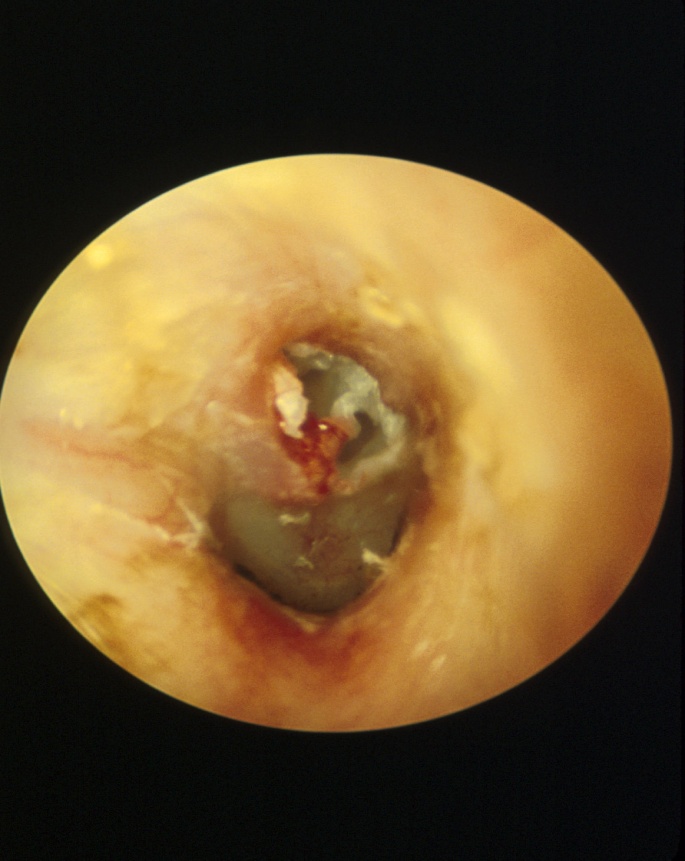

膽脂瘤(cholesteatoma)是一種中耳表皮樣囊腫(epidermoidcyst), 常見的是後天性膽脂瘤(acquired cholesteatoma)。此病的成因是由於耳膜向中耳凹入,形成袋狀空間(retraction pocket),耳膜的鱗狀上皮細胞角質層脫落在這袋狀空間,它通常從耳膜的上部或後部開始,角質層積聚物不斷增加形成中耳表皮樣囊腫,囊腫逐漸擴展至中耳後方的乳突(mastoid cavity)。圖一所示是左耳膽脂瘤,可見白色上皮角質層積聚在這袋狀空間。

■圖一